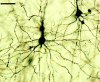

Chronic impairment of forelimb and digit movement is a common problem after stroke that is resistant to therapy. Previous studies have demonstrated that enrichment improves behavioral outcome after focal ischemia; however, postischemic enrichment alone is not capable of enhancing fine digit and forelimb function. Therefore, we combined environmental enrichment with daily skilled-reach training to assess the effect of intensive task-specific rehabilitation on long-term functional outcome. Rats were subjected to either endothelin-1-induced focal ischemia or sham surgery and subsequently designated to enriched-rehabilitation or standard-housing treatment groups starting 15 d after ischemia. Functional assessment of the affected forelimb at 4 and 9 weeks after treatment revealed that ischemic plus enrichment (IE) animals had improved approximately 30% on the staircase-reaching task and were indistinguishable from sham animals for both latency and foot faults in a beam-traversing task. In contrast, ischemic plus standard (IS) animals remained significantly impaired on both tasks. Interestingly, both ischemic groups (IE and IS) relied on the nonaffected forelimb during upright weight-bearing movements, a pattern that persisted for the duration of the experiment. Dendritic arborization of layer V pyramidal cells within the undamaged motor cortex was examined using a Golgi-Cox procedure. IE animals showed enhanced dendritic complexity and length compared with both IS and sham groups. These results suggest that enrichment combined with task-specific rehabilitative therapy is capable of augmenting intrinsic neuronal plasticity within noninjured, functionally connected brain regions, as well as promoting enhanced functional outcome.